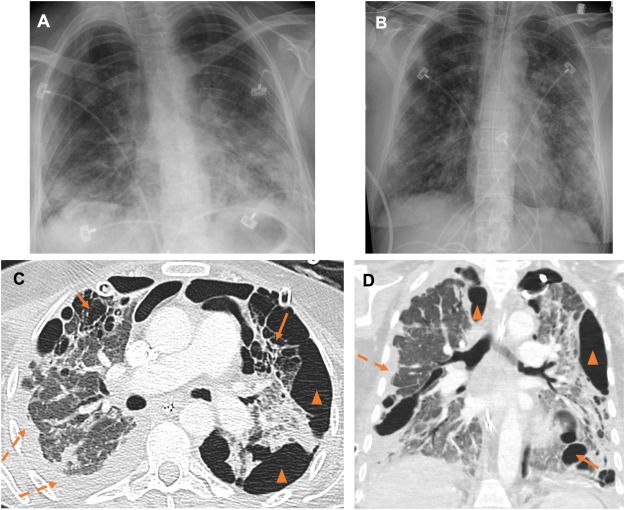

Can you make the diagnosis?